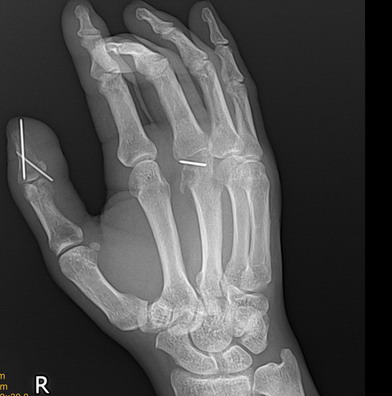

标题: X7184:内固定术后,1月余!

是废用性骨质疏松?还是缺血性坏死?

多发骨折内固定术后,废用性骨质疏松

右手拇指末节及第三掌骨远端钢针内固定术后,第三掌骨远端局限性骨吸收改变伴关节间隙狭窄。

第三掌骨头关节内骨折复位差畸形愈合